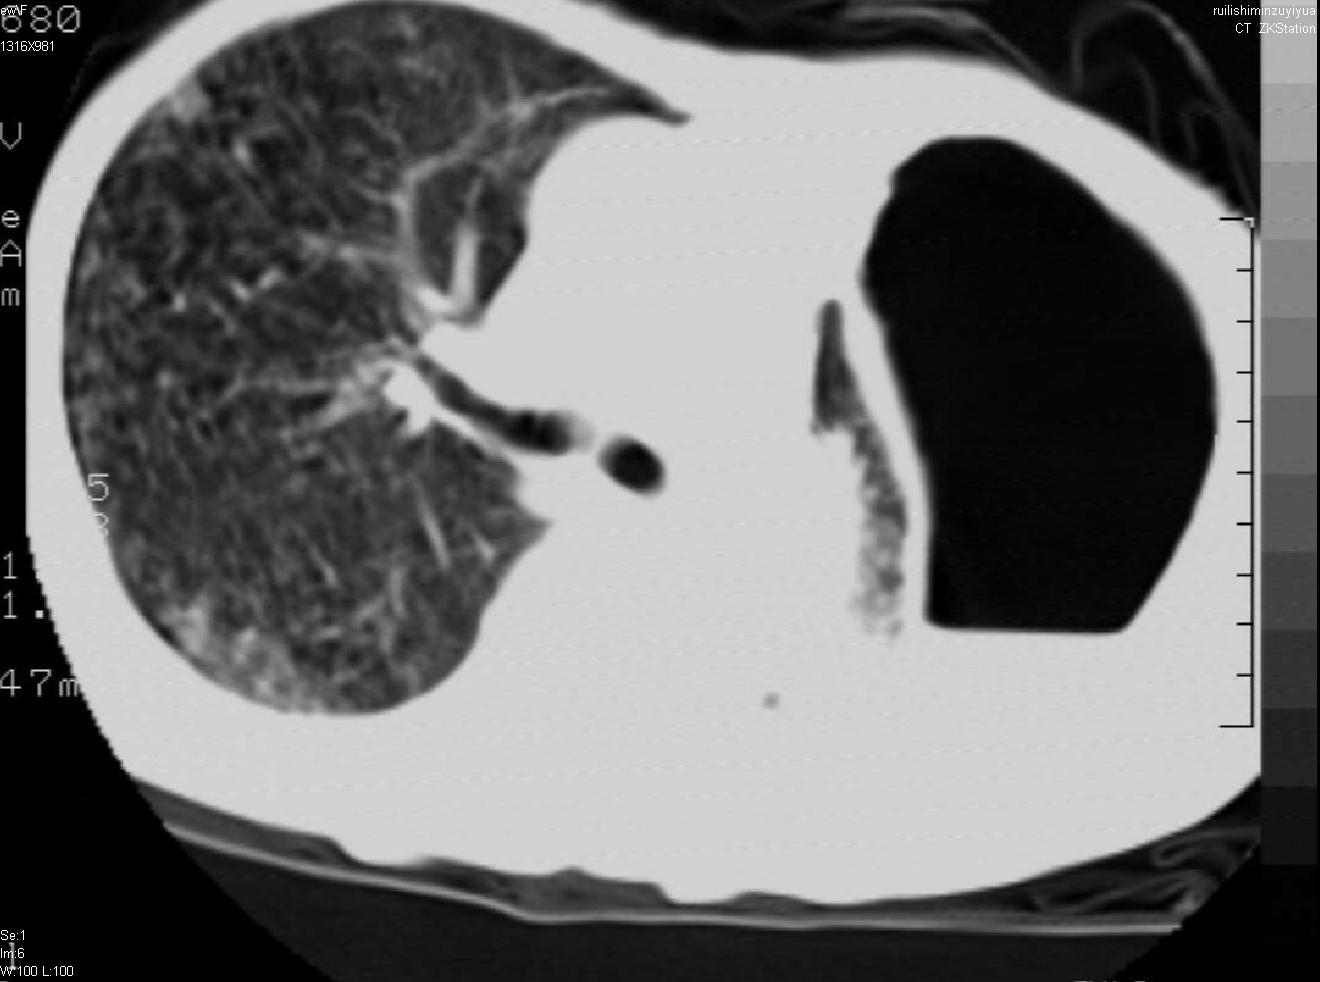

以下是引用天南地北在2007-6-11 23:32:00的发言:[br]1:左侧肺毁损(结核性)伴感染(多发空洞伴液平面)。[br]2:右肺继发型肺结核。

以下是引用avril在2007-6-12 1:17:00的发言:[br]1、左肺毁损。[br]2、左肺多发肺大泡伴自发性气液胸形成。[br]3、右肺继发型结核。